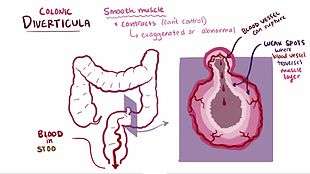

| Large bowel (sigmoid colon) showing multiple diverticula. The diverticula appear on either side of the longitudinal muscle bundle (taenium). | |

Diverticulitis is believed to develop because of changes inside the intestines including high pressures because of faulty contracting of the intestines.[7]

They often evolve from age-related diverticulosis and its associated pathologies resulting from increased intraluminal colonic pressure, including bleeding, abscess, perforation, stricture, fistula formation or impacted fecal matter.[8][9]

Most people with diverticulosis do not have any discomfort or symptoms; however, symptoms may include mild cramps, bloating and constipation. Other diseases such as inflammatory bowel disease (IBD) and stomach ulcers cause similar problems, so these symptoms do not always mean a person has diverticulosis.